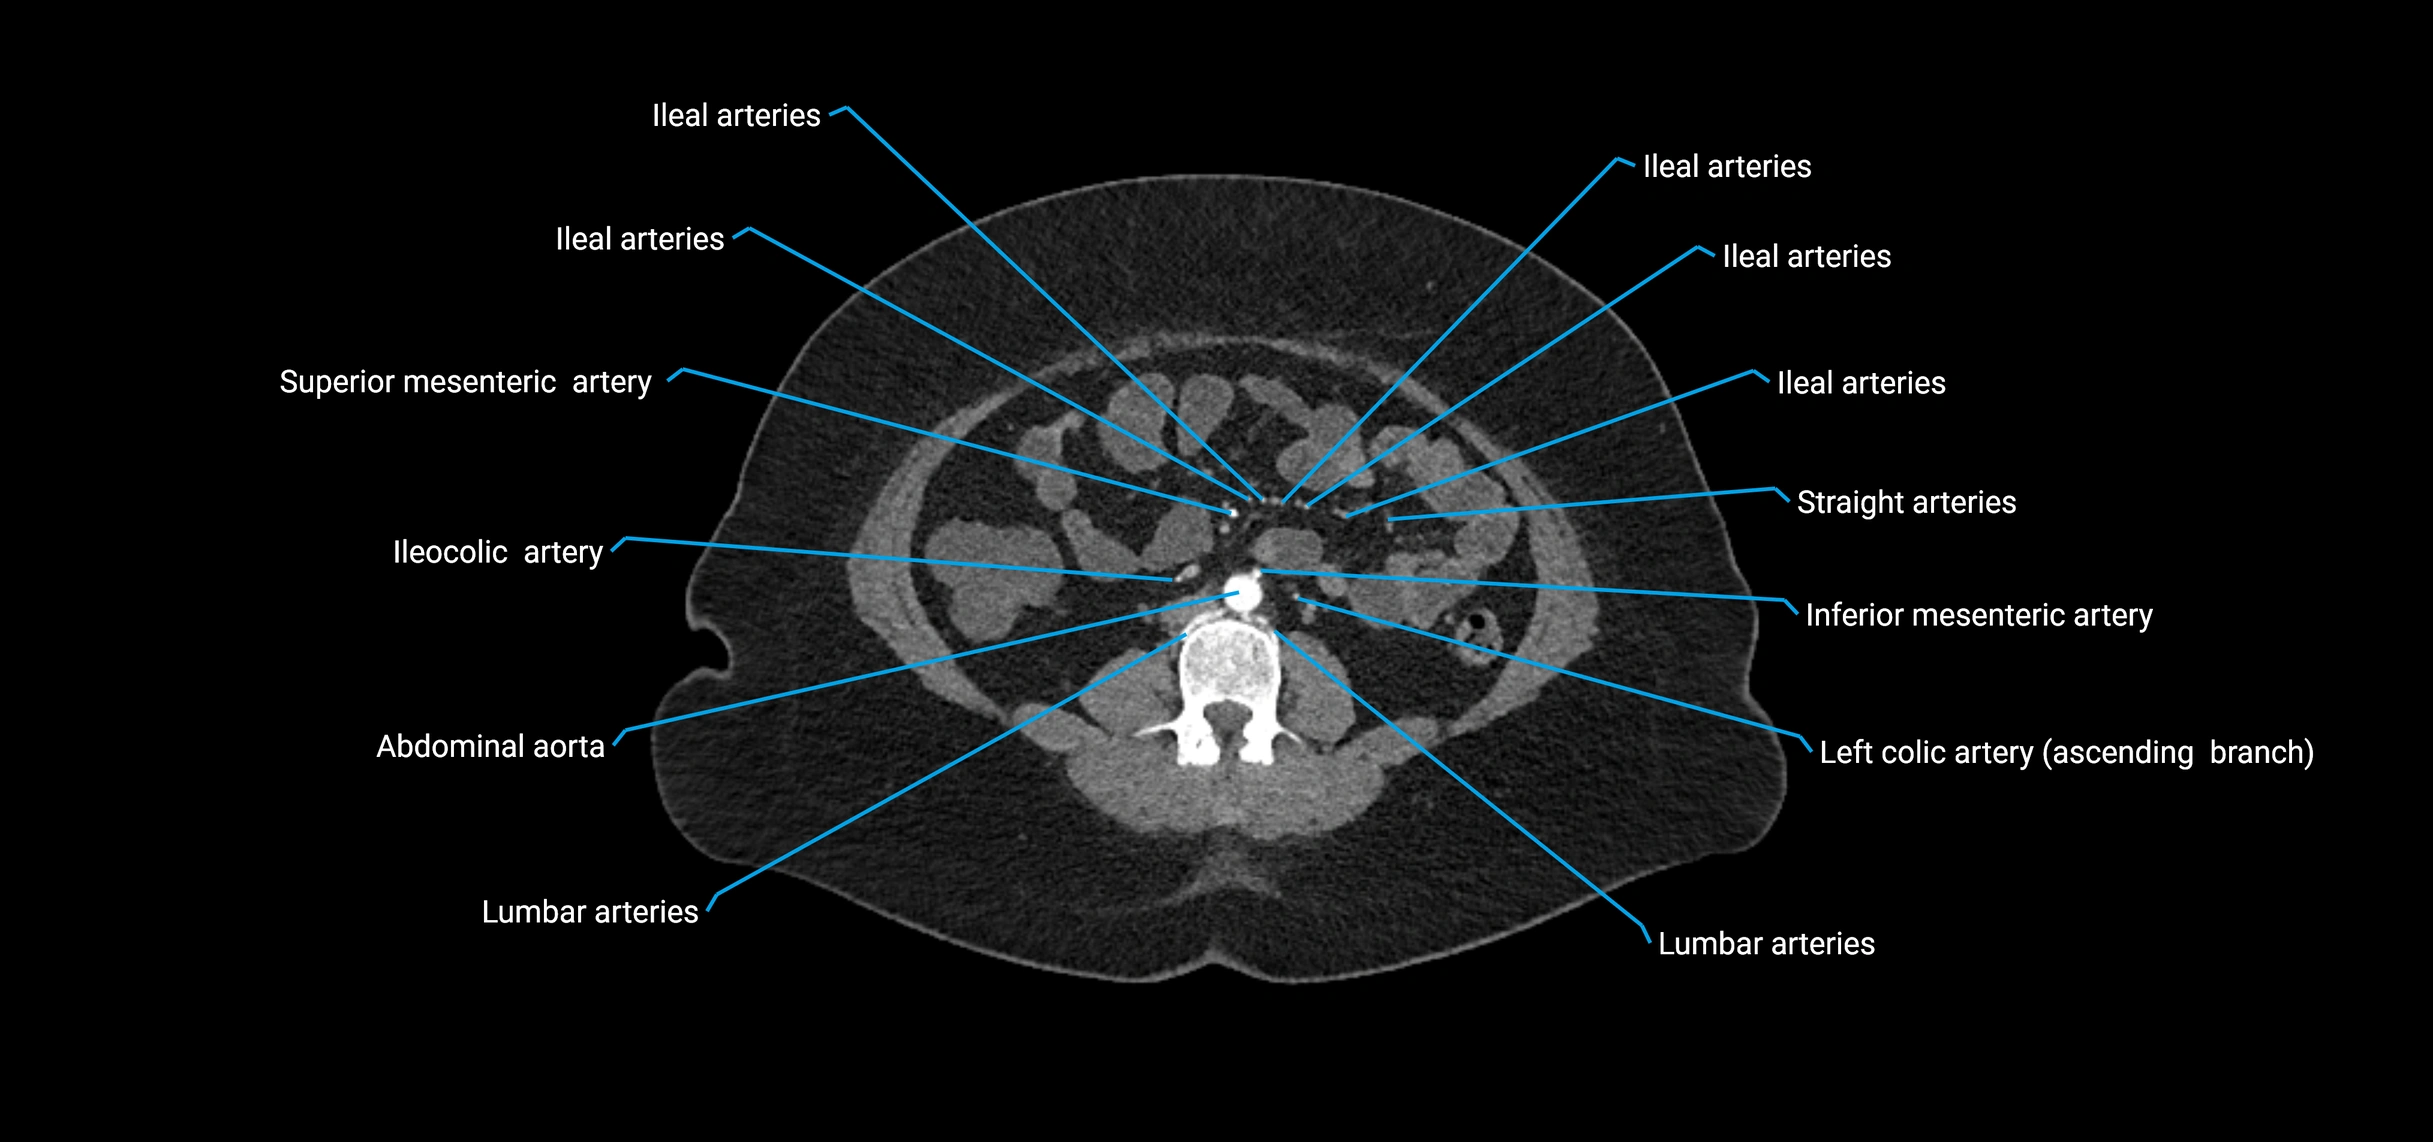

Contrast-enhanced CT (CTA):

• Gold standard for abdominal aortic imaging

• Provides excellent detail of lumen, wall, aneurysm, thrombus, and branch vessels

• Multiplanar and 3D reconstructions help in aneurysm measurement, stent graft planning, and dissection evaluation

• Detects acute rupture, traumatic injury, or occlusion with high sensitivity